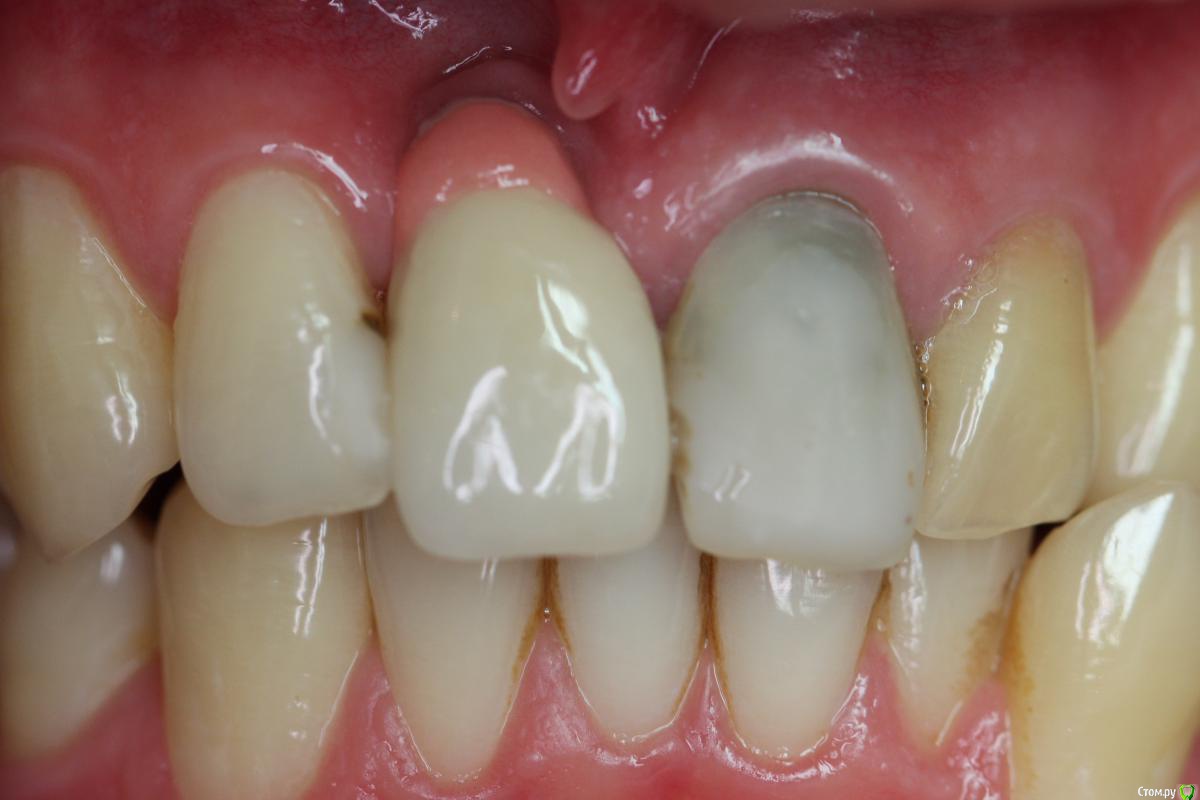

Zorrro Опубликовано 6 марта, 2016 Поделиться Опубликовано 6 марта, 2016 (изменено) Мой постоянный пациент привёл своего сынишку с жалобами на свищь на нёбе.Сделали кт и решили ,что вначале переберём каналы,а через пол года будем посмотреть куда нам двигаться дальше… Эстетика коронки на 11 вполне устраивала пациента,тем более он был уверен,что поставилимплант и вследствии коронку популярный доктор используя новейшие технологии и материалы,позволяющие не прибегать к устаревшим костным и ещё каким-то пластикам.запись к доктору уходила на пол года вперёд и молодой человек чудом втиснулся в этот плотный график,чтобы отхватить немножко и себе этих самых "новейших" технологий под нос. Фото ещё раз показывает,чтосамое главное в успехе частной практики это ВЕРА доктора в себя и то,что он делает.меня же коронка устраивала тем более,потому что переделывать её вместе с имплантом мне крайне не хотелось.обошлись комментарием про усиленную гигиену и регулярные наблюдения раз в пол года. итак занялись посильным трудом:отмыли 21 и 22,констрикция убежала за 50.02,остановились на 70.02 стальными файлами отступя 1мм,метапекс,через 2 недели irm и стекловолокно нафуджи+,филтек.договорились про контроль через пол года и коронки если всё ок. Ещё немного срезов до и преимущество кт перед прицельными снимкамиИ сразу после. Про коронки и корневой герметизм пациент не понял и решил оставить бломбы на месте. Изменено 6 марта, 2016 пользователем Zorrro 1 Ссылка на комментарий